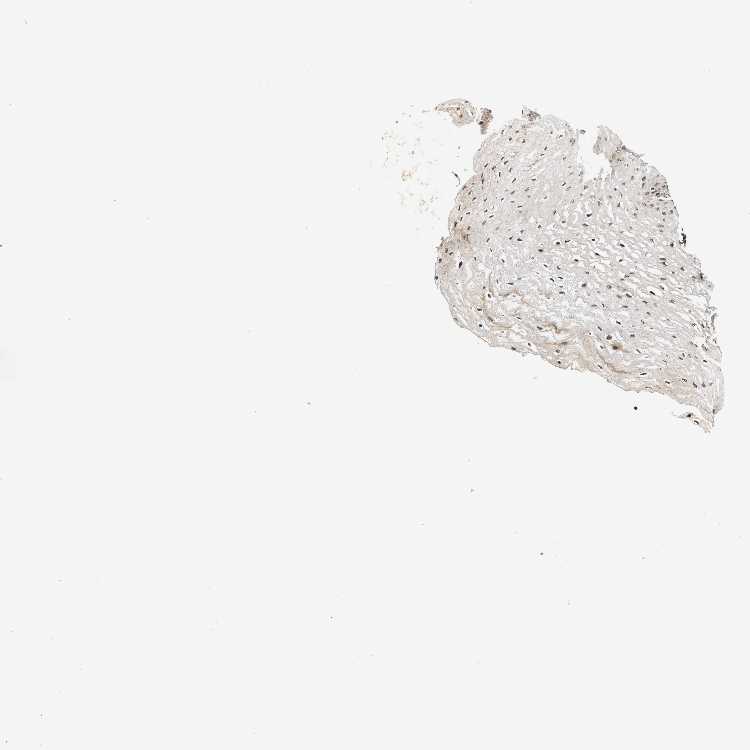

ESOPHAGUS - Antibody stainingi

Antibody staining in the annotated cell types in the current human tissue is reported as not detected, low, medium, or high, based on conventional immunohistochemistry profiling in selected tissues. This score is based on the combination of the staining intensity and fraction of stained cells.

Each image is clickable and will lead to virtual microscopy that enables deeper exploration of all samples and also displays staining intensity scores, fraction scores and subcellular localization as well as patient and tissue information for each sample.

Antibody HPA020338

Squamous epithelial cells Medium